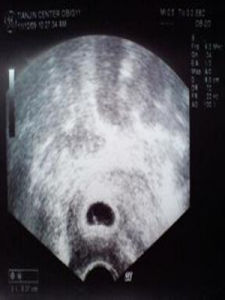

2、B超觀察:這種方法一般是針對有特殊狀況的準媽媽,而且只能在醫院進行。